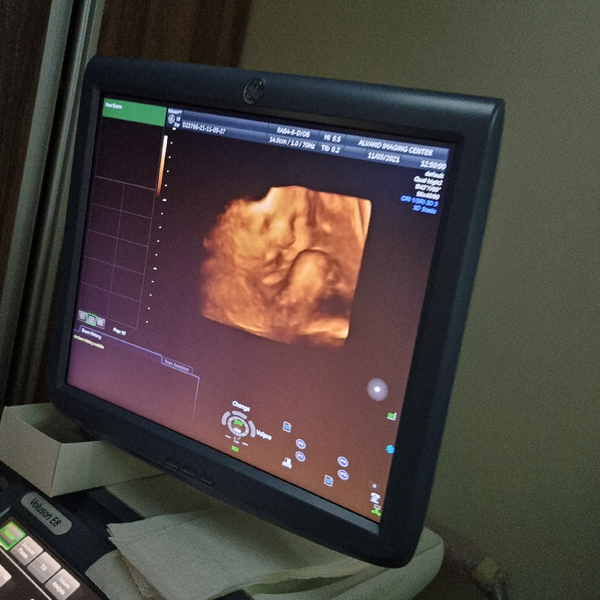

تصویر تشکیل شده در مانیتور قابل مشاهده است.

ممکن است رنگی یا سیاه و سفید باشد. این تصاویر به عنوان بخشی از پرونده جنین ذخیره می شود.

دستگاههای پیشرفته سونوگرافی ۳ بعدی و ۴ بعدی با رزولوشن بالا برای مشاهده دقیق آناتومی جنین.